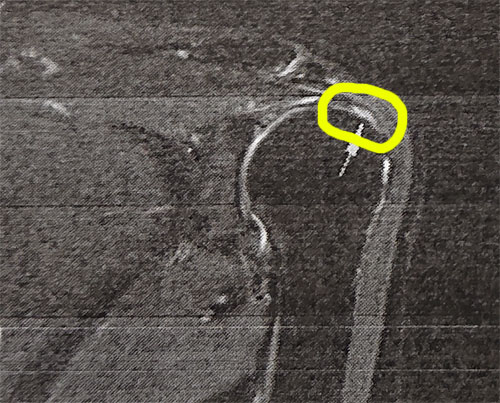

毎日、これでもか!ってぐらい暑いんですけど。むっちゃんも熱中症で病院にお世話になった事があると、今日のリーダーコラムで知りましたが、気を付けないとね。先週のMRIの結果が、「左肩関節腱板損傷」という診断結果。てっきり、ン十肩と思いきや、腱板部分断裂で、自然治癒は望めないから、保存療法か関節鏡下腱板断裂手術。手術した場合、日常生活で不便なく生活できるまでは2~3ヶ月、さらにスポーツや重労働までは6ヶ月くらい。腱板断裂部には負担がかからず、効果が高い、肩の根本である肩甲骨の動きを良くするリハビリテーションがあるようで、それを受けて、近辺の筋力Upで負荷がかからないようにするとか。